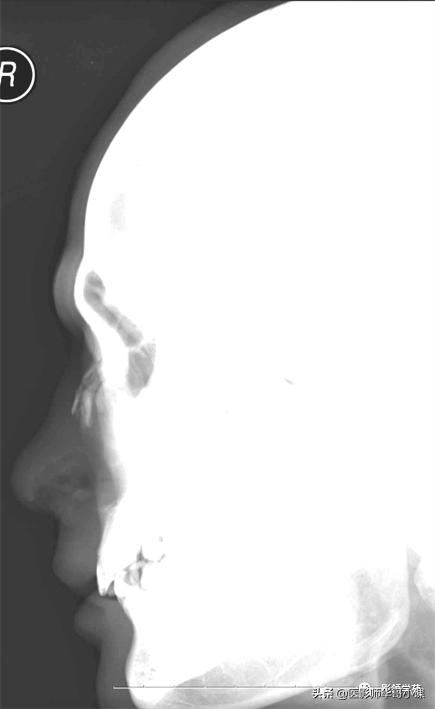

鼻骨正常侧位

X线平片:侧位